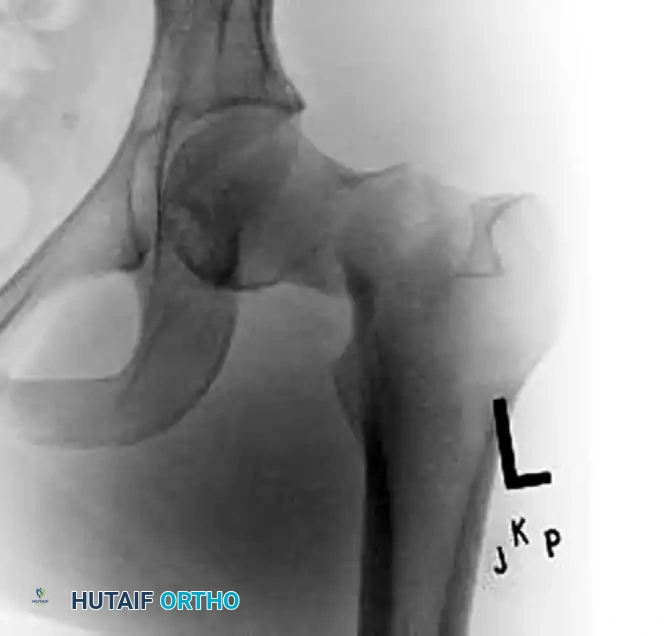

Figure 55-15B: Postoperative anteroposterior radiograph revealing significant femoral neck shortening. The dynamic compression allowed by the partially threaded screws has resulted in a loss of femoral offset and abductor lever arm.

Significant shortening alters the biomechanics of the hip joint by decreasing femoral offset. This reduces the lever arm of the hip abductors (gluteus medius and minimus), resulting in abductor weakness, a persistent Trendelenburg gait, increased energy expenditure, and diminished patient-reported outcome measures (PROMs).